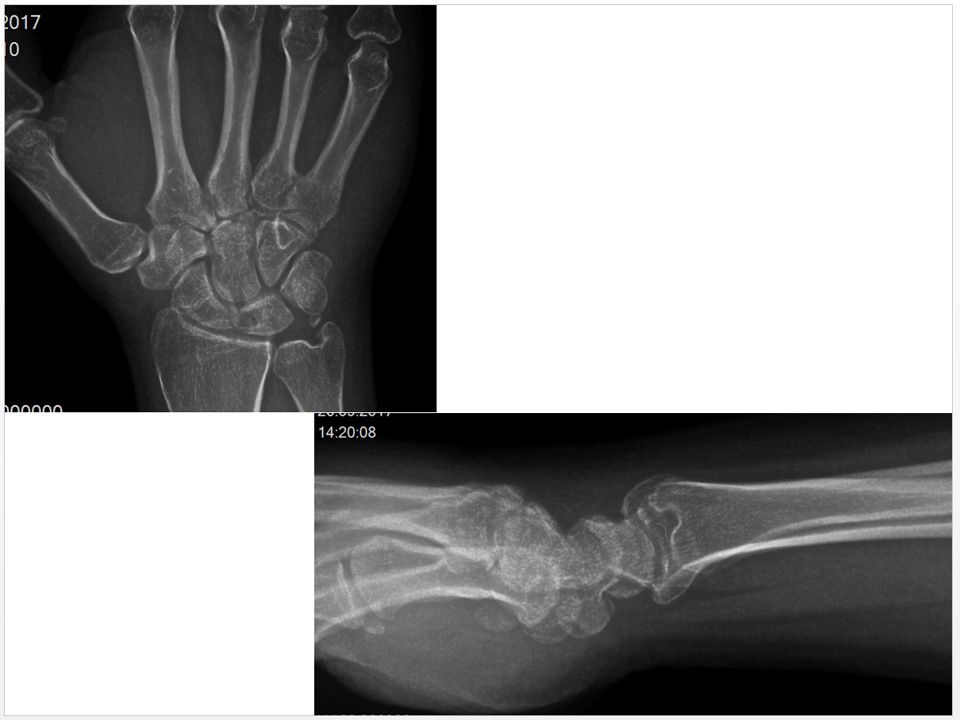

25 yaş, erkek, , sağ el dominant2.5 yıl önce burkulma sonrası sağ el bilek dorsal orta hatta mevcut ağrıFTR, istirahat ateli ve NSAID’e rağmen geçmemişWatson shift testi +, parmak ekstansiyon testi +